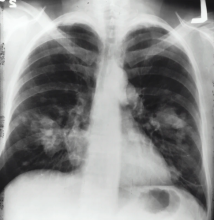

Professor Tristan D. Yan, a consultant cardiovascular and thoracic surgeon based at the Royal Prince Alfred Hospital in Sydney, Australia, prepared a series of twelve surgical videos on the technical aspects within thoracic surgical oncology for educational purposes. Aspects of these videos are quite unique in that they cover a wide range of clinical pathology and surgical techniques.

The series begins with the first video available now, with a new video published every two weeks hereafter. Joel Dunning, cardiothoracic surgeon at the James Cook University Hospital, UK, provides the narration in the series.